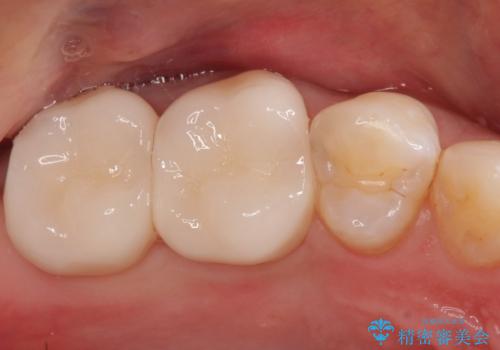

- 奥歯がかけたことを主訴に来院されました。

オールセラミッククラウンにて修復治療を行っております。

歯の破折強度を高めるためにクラウンによる修復を希望され、治療を行っております。